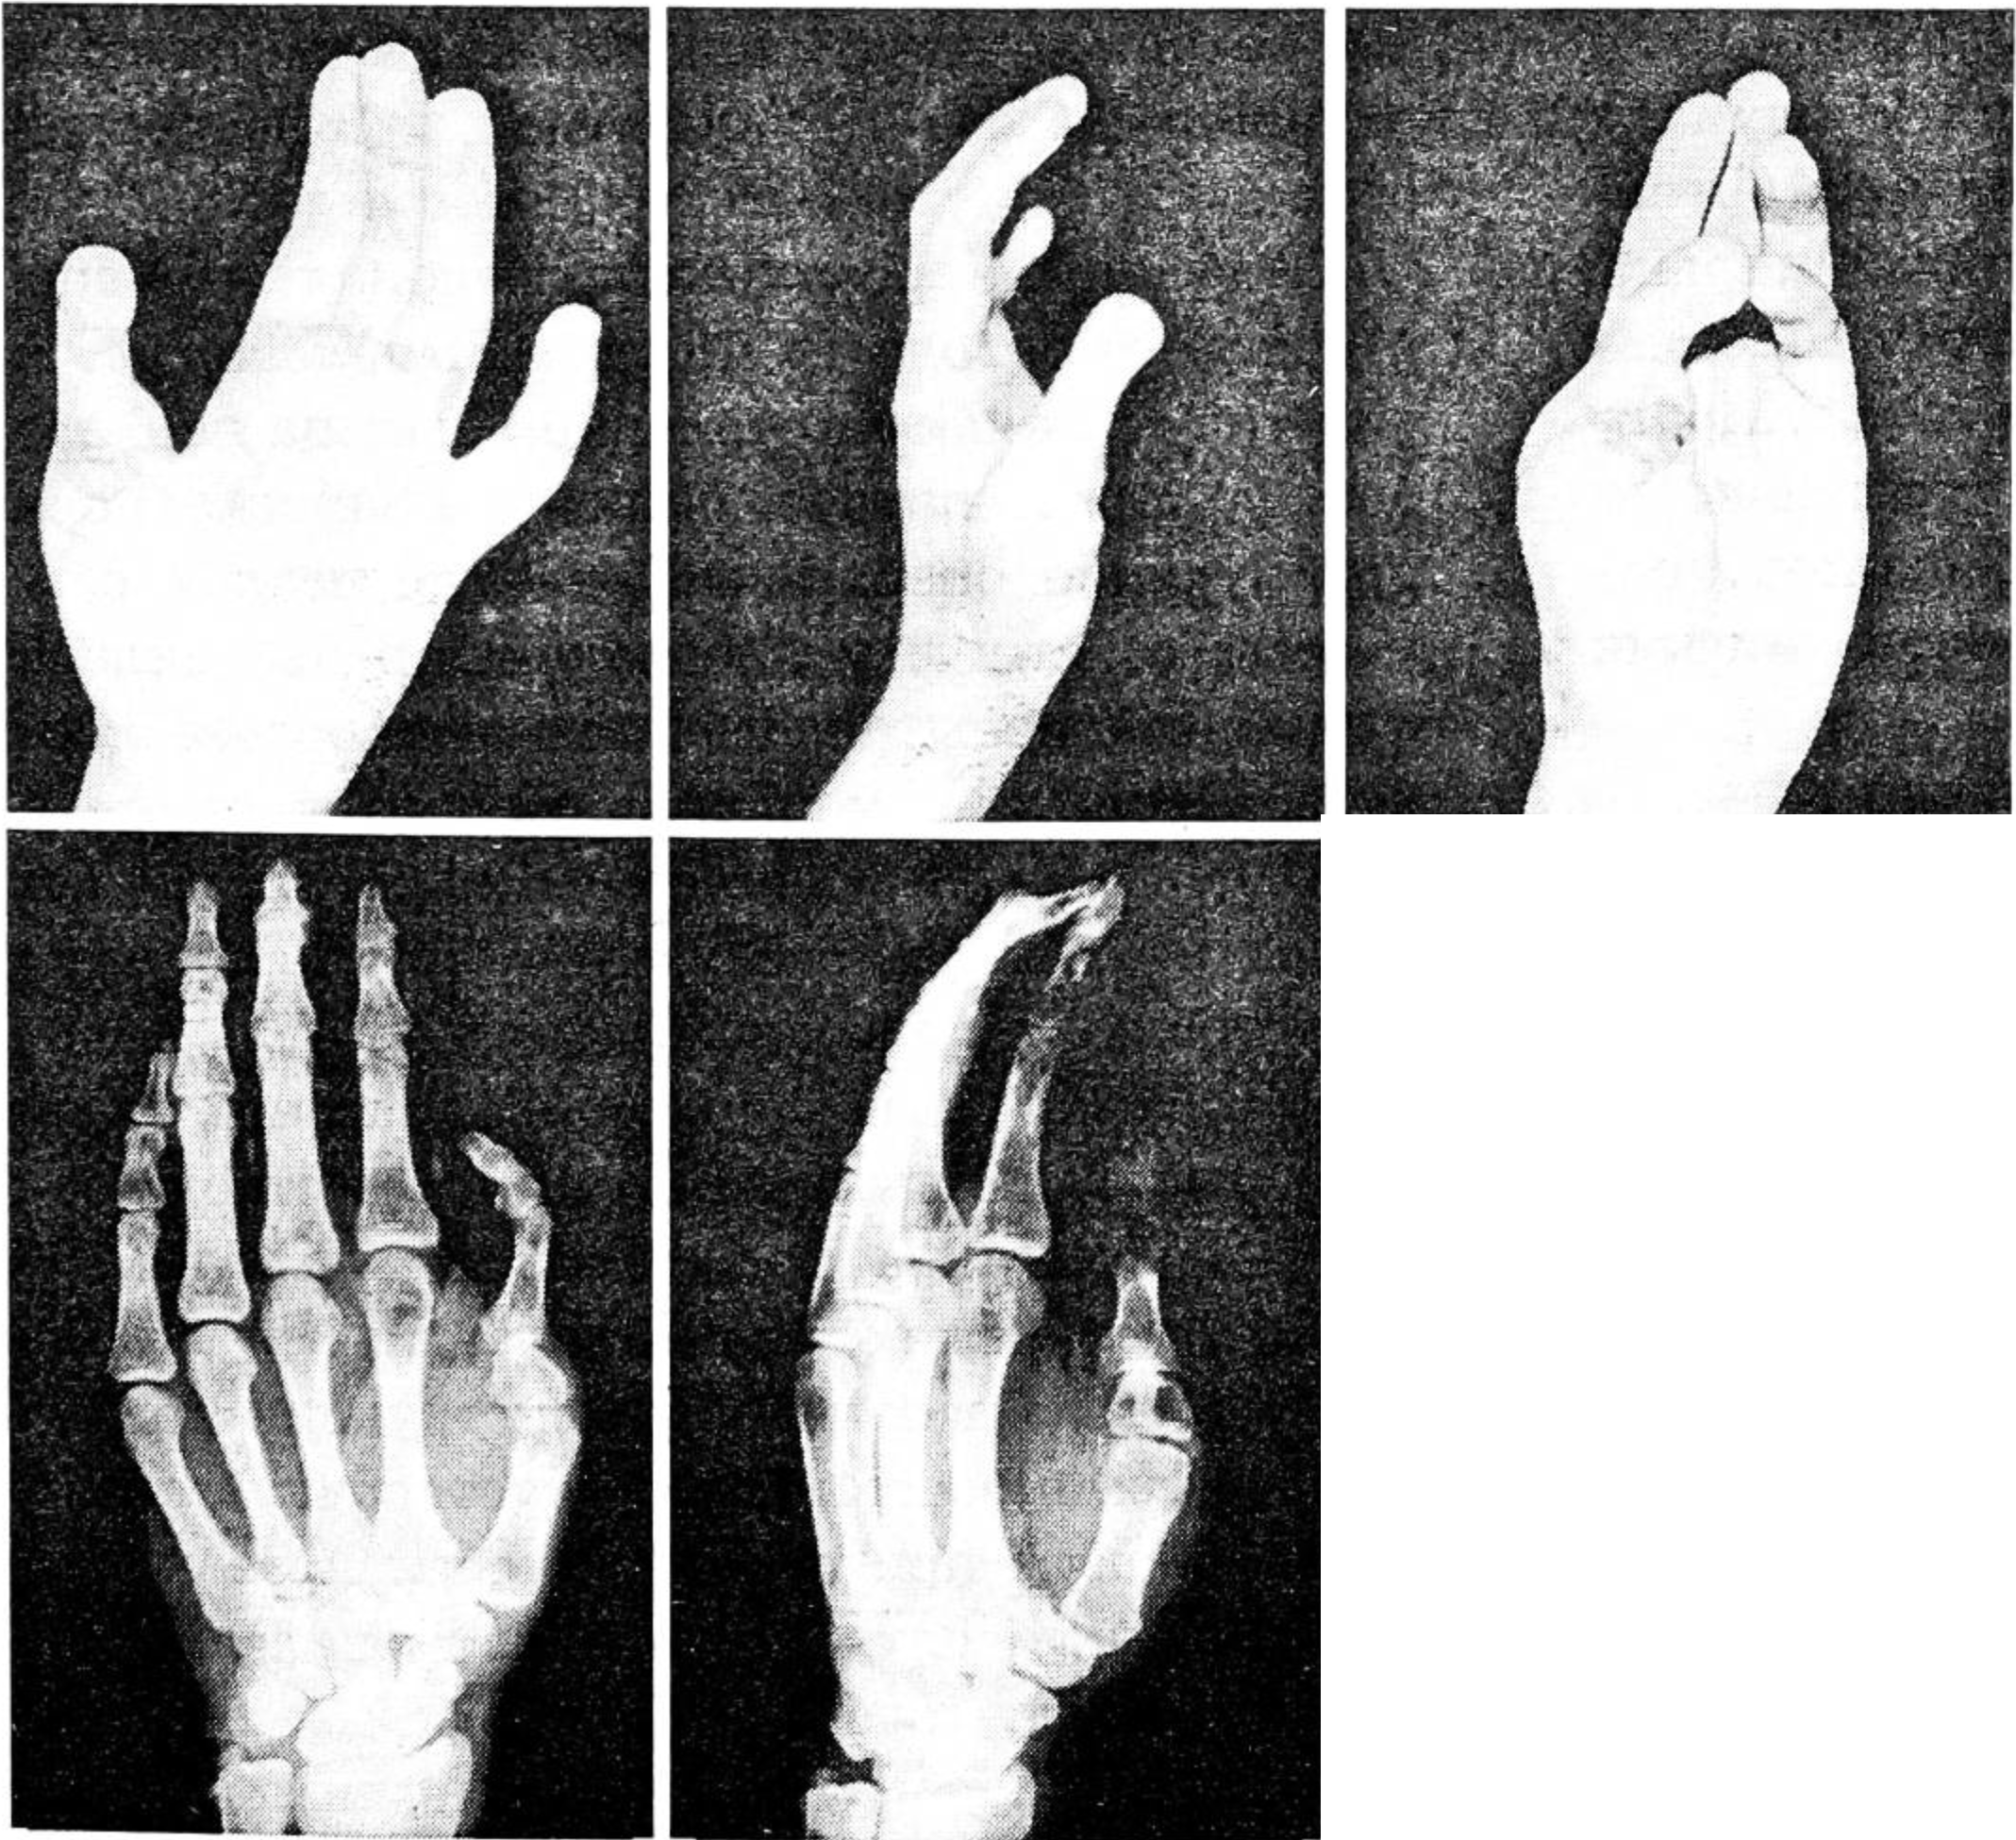

Больной Г., 34 лет, поступил в клинику 5.12.89. с диагнозом: травматический отрыв I пальца левой кисти на уровне основной фаланги, рваная рана ладонной поверхности II-IV пальцев с повреждением сухожилий сгибателей II и III пальцев (рис. 2). Травма (бытовая) получена в результате попадания кисти в циркулярную пилу. При поступлении произведены хирургическая обработка ран, шов сухожилий глубоких сгибателей II-III пальцев. 11.12.89. выполнена свободная пересадка II пальца правой стопы на культю основной фаланги I пальца левой кисти. Послеоперационное течение гладкое, пересаженный трансплантат прижил полностью. При контрольном обследовании через 1 год больной выполняет восстановленным пальцем все виды схватов. Возможно противопоставление I пальца всем остальным, хотя движения в его межфаланговых суставах отсутствуют. Отмечаются движения в сохранившемся первом пястно-фаланговом суставе объемом 30°. На рентгенограмме определяется полная консолидация основной фаланги пересаженного пальца с культей основной фаланги I пальца (рис. 3). Пациент работает по прежней специальности.

Рис. 2. Больной Г.: внешний вид и рентгенограммы поврежденной кисти до операции.

Рис. 3. Тот же больной: внешний вид, рентгенограммы кисти и функциональный результат через 1 год после операции.